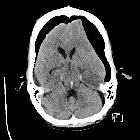

Duret hemorrhage is a small hemorrhage (or multiple hemorrhages) seen in the medulla or pons of patients who are rapidly developing brain herniation, especially central herniation.

Raised supratentorial pressure causes the brainstem and mesial temporal lobes to be forced downwards through the tentorial hiatus. As a result of this shift, it is believed that perforating branches from the basilar artery and/or draining veins are damaged with resultant parenchymal hemorrhage. Most commonly it is seen in patients with severe herniation 12 to 24 hours prior to death .

The classical appearance of a Duret hemorrhage is a single small, round hemorrhage located in the midline of the medulla or pons near the pontomesencephalic junction. Often, however, these hemorrhages can be multiple or even extend into the cerebellar peduncles.